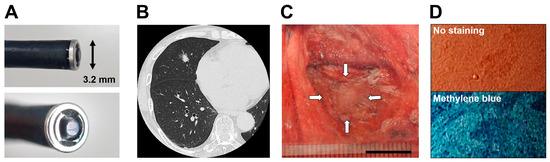

2.2. Endocytoscopy

We used a catheter-type endocytoscope (prototype XEC-300-2, Olympus Medical Systems, Tokyo, Japan) with a length of 380 cm and an outer diameter of 3.2 mm at the tip. An endocytoscopic image can provide an observation field, an observation depth, and a horizontal resolution of 300 × 300 μm, 0–30 μm, and 4.2 μm, respectively, with 450-fold magnification on a 14-inch monitor (Figure 1A).

2.3. Acquisition of the Endocytoscopic Images

Computed tomography (CT) images showed the location of a target lesion (Figure 1B). Thoracic surgeons performed surgical resection of the lesion. A pathologist cut into the center of the lesion in the resected specimens. In cases that required rapid intraoperative diagnosis, the part that remained following the removal of a portion of the resected tissues for frozen sections by the pathologist was used for endocytoscopic observation (Figure 1C). Without staining, no relevant findings regarding the lesion were revealed. Methylene blue staining revealed dark-blue cell nuclei at the same lesion site (Figure 1D). Therefore, we stained the cut surface with a drop of 0.25–0.5% methylene blue using a 1-mL syringe with a 23-G needle. The tip of the endocytoscope was placed directly on the cut surface, and we immediately observed the stained lesion on the monitor screen. Additional drops of methylene blue were added for large lesions as necessary. We attempted to observe the normal lung area in a similar manner. These observations were recorded using a video recorder (IMH-20; Olympus Medical Systems). The procedure was completed within 3 h of the resection. The specimens were fixed with formalin and stained with H&E.

Figure 1. Endocytoscopy (ECS) overview for resected lung specimens. (A) Appearance of an endocytoscope (Source: courtesy of Olympus Medical Systems). (B) High-resolution computed tomography of a patient with adenocarcinoma. (C) Macroscopic appearance of a lesion (white arrows: adenocarcinoma) resected from the patient. Scale bar: 10 mm. (D) Endocytoscopic images of the lesion with and without methylene blue staining.